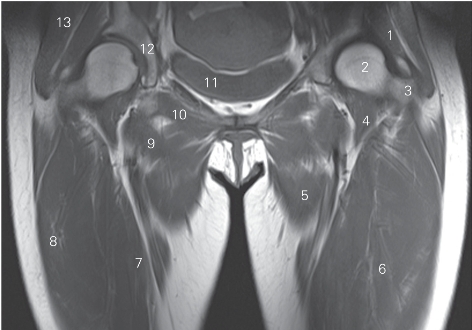

图5-15 经股骨颈的冠状断层MR T1加权图像

1 臀小肌 gluteus minimus 2 股骨头 head of femur

3 大转子 greater trochanter 4 髂腰肌 iliopsoas

5 大收肌 adductor magnus 6 股中间肌 vastus intermedius

7 股内侧肌 musculus vastus medialis 8 股外侧肌 vastus lateralis

9 耻骨肌 pectineus 10 闭孔外肌 obturator externus

11 膀胱 urinary bladder 12 髋臼 acetabulum

13 臀中肌 gluteus medius